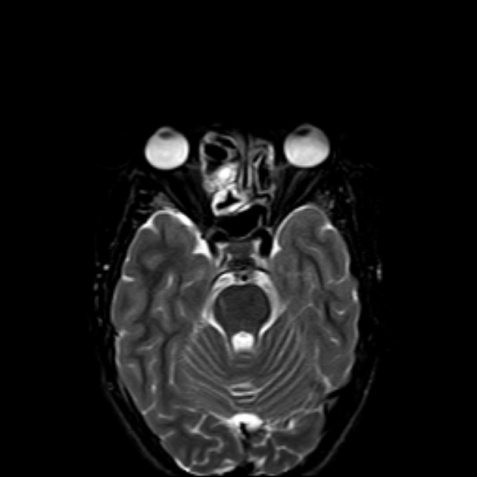

КТ-снимки хронического этмоидита: подробная визуализация